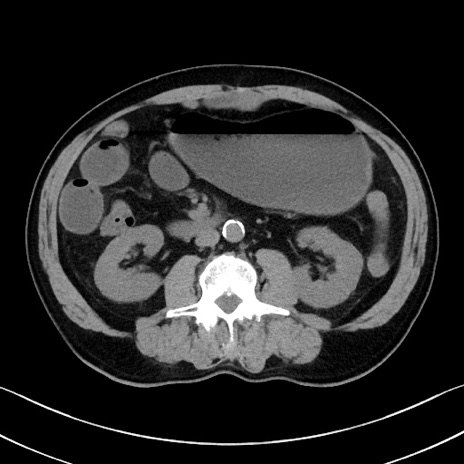

症例35(横断像)

冠状断像

【症例】70歳代 男性

【主訴】腹部膨満、嘔吐

【現病歴】昨日より腹部膨満感出現。本日増悪し、仙痛出現。嘔吐あり、受診。

【既往歴】糖尿病、胆摘後

【身体所見】BP 149/80mmHg、HR 74/min、BT 35.9℃、腹部:膨満、軟、圧痛なし。腸雑音減弱あり。上腹部正中切開瘢痕あり。

【データ】WBC 13500、CRP 1.72